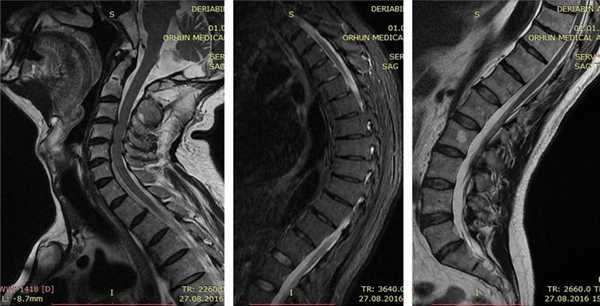

После основных методов обследования назначаются дополнительные. Среди них главное место занимает лучевая диагностика: рентгенологическое исследование позвоночника и магнитно-резонансная томография. На снимках можно увидеть, что позвонки имеет клиновидную форму, характерную именно для данного заболевания. Также выявляются и другие сопутствующие проблемы, такие как остеохондроз, грыжи дисков, спондилолистез, остеофиты и т.д.

Болезнь Шейермана-Мау – это заболевание, при котором наблюдается прогрессирующее кифотическое искривление позвоночного столба. Возникает в пубертатном возрасте, одинаково часто встречается у мальчиков и девочек. На ранних стадиях симптоматика стертая. В последующем появляются боли и видимая деформация позвоночника – сутулая круглая спина, в тяжелых случаях возможен горб. В отдельных случаях развиваются неврологические осложнения. Для подтверждения диагноза выполняют рентгенографию, КТ и МРТ. Лечение обычно консервативное, при тяжелых деформациях проводятся хирургические вмешательства.

В норме тела позвонков имеют почти прямоугольную форму, их задние и передние отделы примерно равны по высоте. При болезни Шейермана-Мау несколько грудных позвонков уменьшаются по высоте в передних отделах, приобретают клиновидную форму. Угол грудного изгиба увеличивается до 45-75 градусов. Спина становится круглой. Нагрузка на позвоночник перераспределяется. Ткань межпозвонкового диска «продавливает» замыкательную пластинку и выпячивается в тело ниже- или вышележащего позвонка, образуются грыжи Шморля. Связки, удерживающие позвонки, компенсаторно утолщаются, что еще больше затрудняет восстановление и дальнейший нормальный рост позвонков. Форма грудной клетки меняется, что может приводить к сдавливанию внутренних органов.

Врач опрашивает пациента с подозрением на болезнь Шейермана-Мау, выясняя жалобы, историю развития патологии и семейный анамнез (были ли случаи заболевания в семье). Ведущим методом инструментальной диагностики является рентгенография позвоночника. На рентгенограммах определяется характерная картина: увеличение угла грудного кифоза более 45 градусов, клиновидная деформация трех и более грудных позвонков и грыжи Шморля. Для выявления неврологических нарушений назначают консультацию невролога. При наличии таких нарушений пациента направляют на МРТ позвоночника и КТ позвоночника для более точной оценки состояния костных и мягкотканных структур. Также может быть назначена электромиография. Межпозвонковая грыжа является показанием к консультации нейрохирурга. При подозрении на нарушения функции органов грудной клетки необходима консультация пульмонолога и кардиолога.